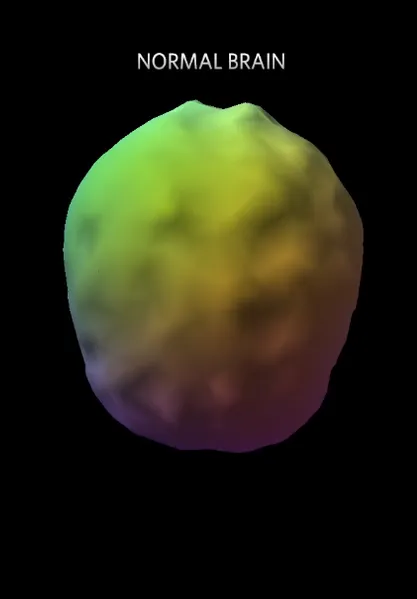

Đây là ảnh não bộ con người bình thường: